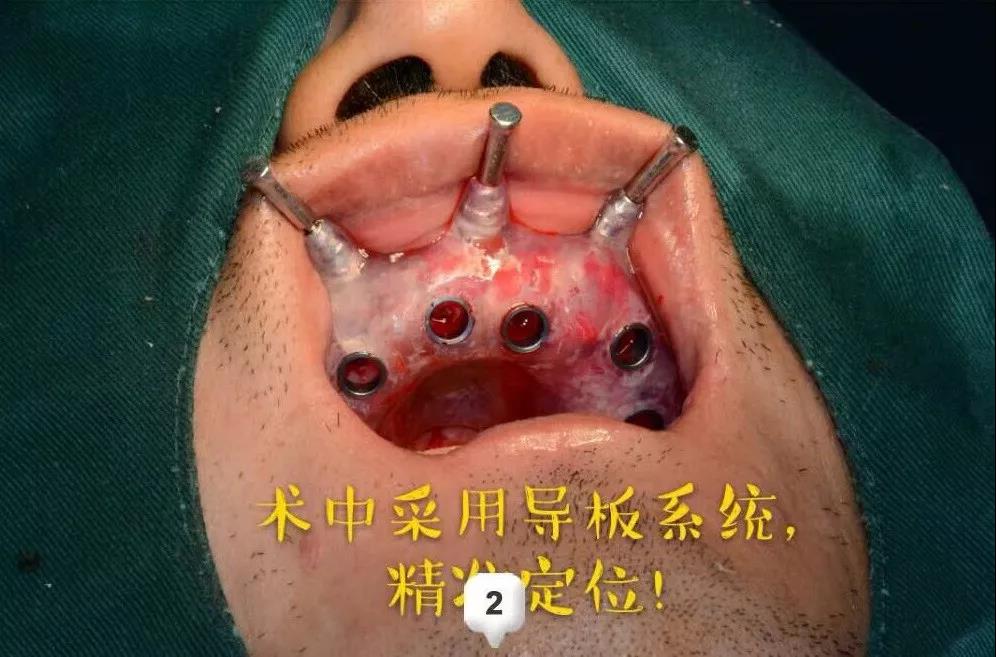

ЁЁЁЁЪЅНрПкЧЛгРаЫТЗдКжжжВПЦЕФВмН№ЗхжїШЮЮЊМжЯШЩњжЦЖЈСЫМДАЮМДжжЕФжжжВЗНАИЃЌдкАЮГ§ЛМбРЕФЭЌЪБжВШыжжжВЬхЃЌВЩгУALL-ON-6ШЋПкжжжВММЪѕХфКЯ3DДђгЁММЪѕКЭЪ§зжЛЏжжбРЕМАхЃЌШЋПкжжжВМгЩЯМДПЬИКжиЃЌЪЧЗЧГЃгааЇЕФбРСажиНЈЗНАИЁЃ

ЁЁЁЁЕквЛДЮКФЪБСНИіЖраЁЪБЃКЯШНјааСЫЪѕЧАЕФВтСПЦРЙРЃЌжИЖЈЪжЪѕЗНАИ;ЪѕжаВЩгУЪ§зжЛЏжжбРЕМАхЃЌОЋзМЖЈЮЛ;ж№МЖБИЖДЃЌжВШыжВЬхЃЌХЄСІИДКЯЭъГЩжВШыЩЯАыПкЁЃ

ЁЁЁЁОЙ§вЛжмЕФЛжИДЪБМфЃЌНјааСЫЯТАыПкЕФжжжВЃЌВмжїШЮСЊКЯжжжВЬхМгЙЄГЇЕФММЪІИЯЙЄжЦзїЭъГЩСЫШЋПкЮобРђЂЕФМДПЬаоИДЃЌРњЪБ12ИіаЁЪБЃЌЪжЪѕНсЪјЪБвбОЪЧЭэЩЯ10ЕуЖрЃЌЛМепгжПЊГЕИЯЛиСЫББОЉЁЃ